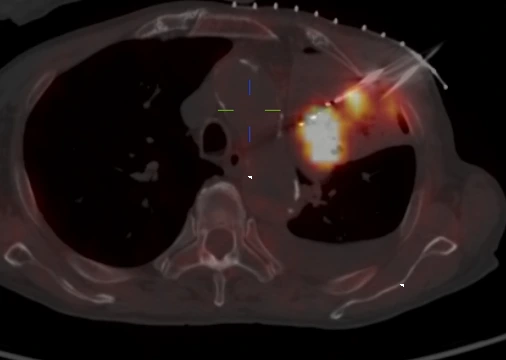

肿瘤微创的核心是采用先进的影像设备进行引导,从最初的X机到超声、CT乃至MRI,我们一直在探索新的影像设备对疾病治疗早期诊断和精准定位。PET/CT在微创领域的应用,标志的肿瘤微创进入分子影像引导的全新领域,最终实现患者获益。

PET/CT引导优势

诊断准确、定位清晰

肿瘤微创治疗之所以微创就是对病灶实施精确打击,PET/CT好比相控阵雷达,可以清晰分辨异常和正常组织

PET/CT在融合CT图像后可以完成术中增强扫描,避开危险血管